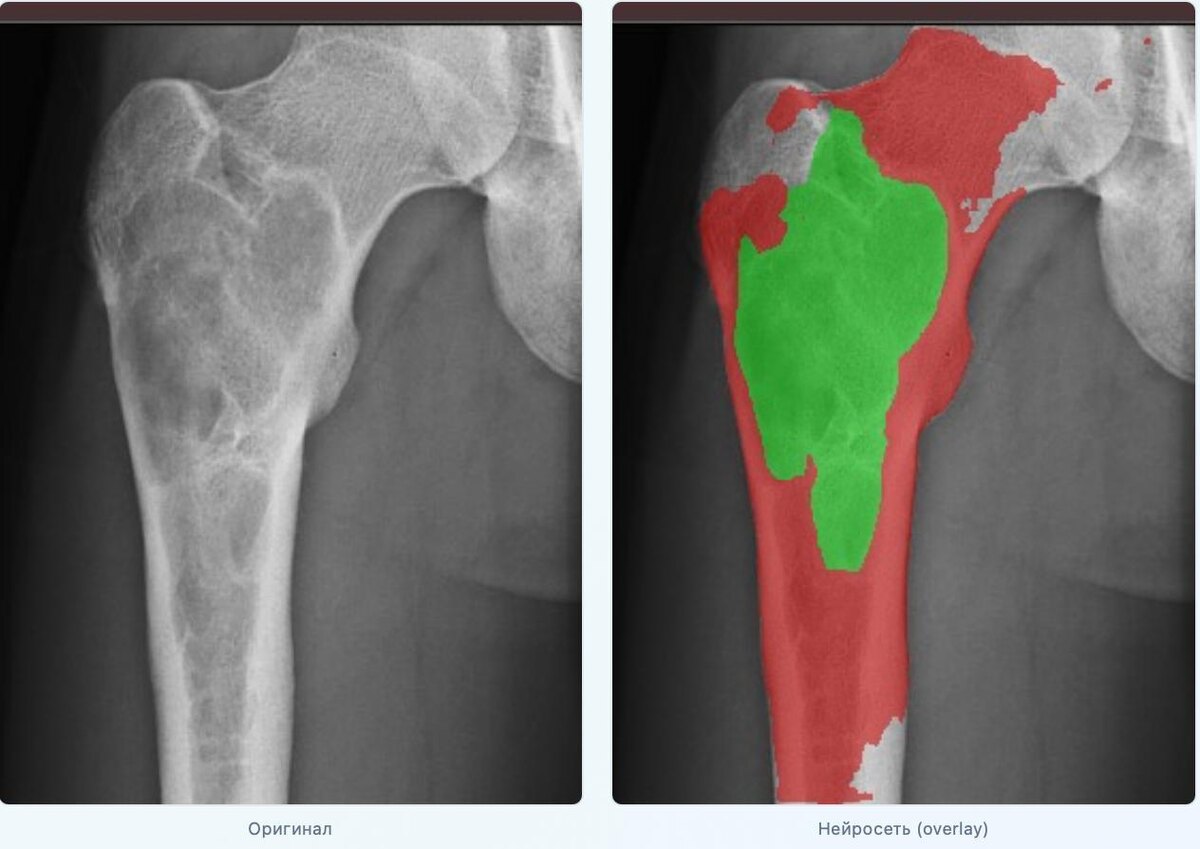

🧬 Наш ответ на эту ситуацию — ИИ-инструмент компьютерного зрения: мы обучили нейросеть U-Net с энкодером ResNet50 на рентгенах с ручной разметкой (фон, кость, киста). Валидация по 5-fold CV. Финальная точность — mIoU ≈ 80,6%.

⚡️ Метрики: Нейросеть считает 🟡 RDS — насколько плотность в зоне кисты приближается к плотности здоровой кости, и 🟡 RAI — долю площади кисты относительно кости. Эти числа можно сравнивать «до/после» без угадывания.

💡 Клинический пример (см снимки): Пациент с кистой правой бедренной кости. Первая рентгенограмма с оценкой нейросети — исходное состояние. Контроль через 6 месяцев после биостимуляции PRF. Нейросеть зафиксировала: 🟡 ΔRDS +0.184 (относительная плотность выросла), 🟡 ΔRAI -0.179 (относительная площадь уменьшилась на 18%). Объективные цифры, а не «кажется». Да, модель еще несовершенна - мы работаем над этим. Но инструмент у нас появился в арсенале отличный.